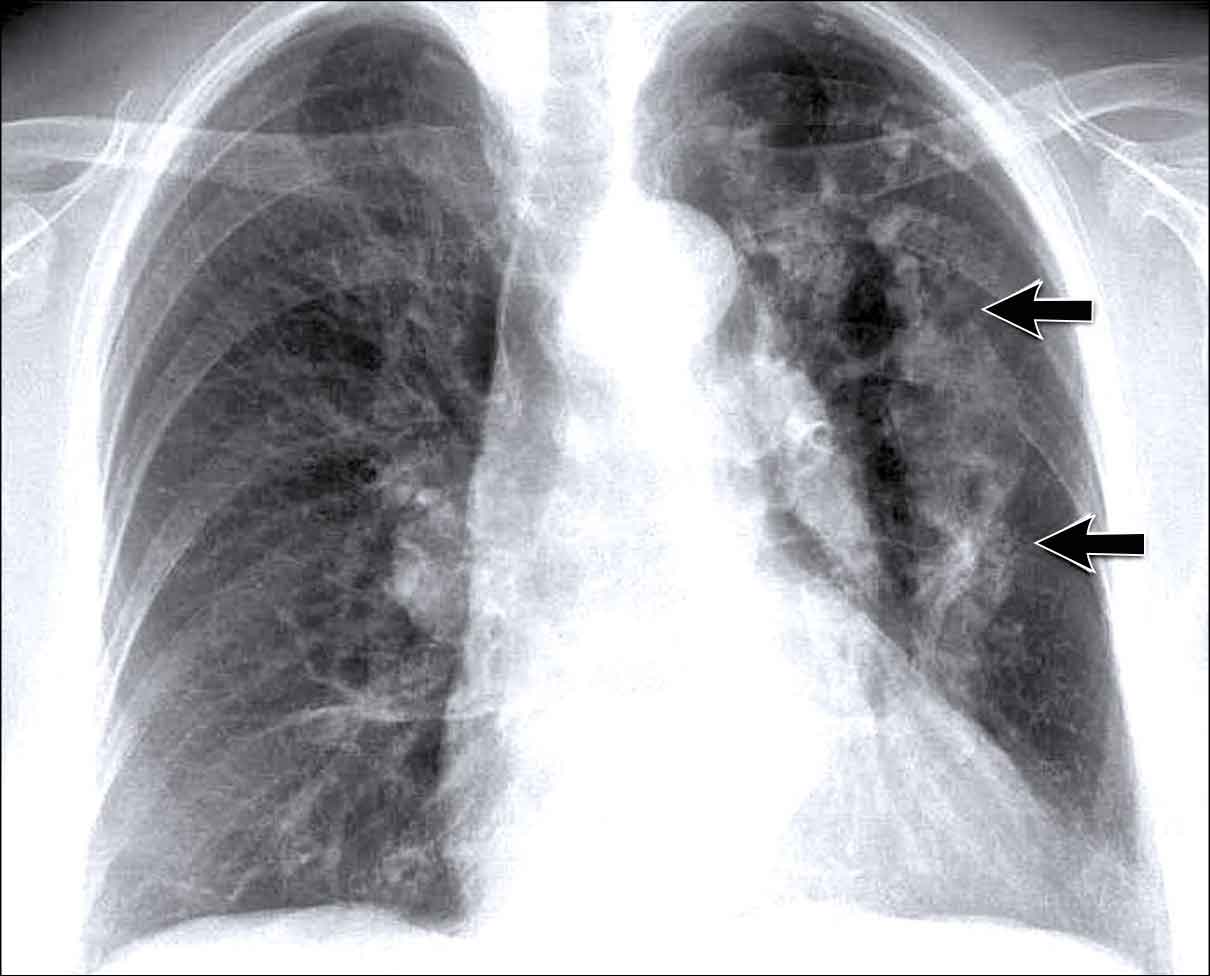

Case Example: Subtle Signs of Congestive Heart Failure

Begin by reviewing these current chest radiographs.

Based solely on these images, one might suspect congestive heart failure (CHF), though the findings are subtle.

Now review the previous study…

Scrolling between the current and prior films significantly increases diagnostic confidence in your diagnosis of congestive heart failure.

Key comparative findings include:

- Cardiac size: Slightly increased compared to the previous study; however, cardiomegaly was already present.

- Pulmonary vasculature: Mild vascular engorgement suggesting elevated pulmonary venous pressure.

- Interstitial markings: Subtle signs of interstitial edema .

- Pleural effusions: Bilateral small effusions, with subtle changes in the inferoposterior borders of the lower lobes, suggesting fluid accumulation.